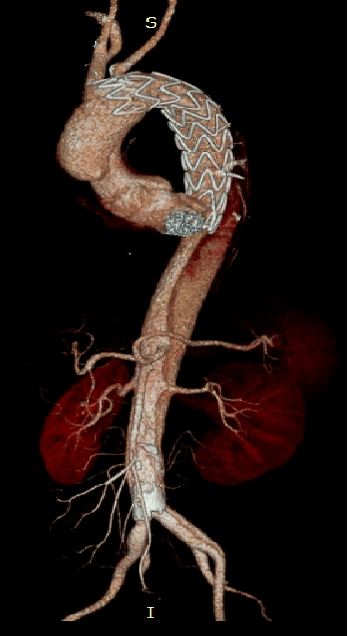

男性,44岁,慢性B型夹层。2010年12月行TEVAR术。

2013年5月发现RTAD,未处理。2015年2月死亡。

▎病例二

男,52岁,慢性夹层。2015年8月入院,4年前曾因B型层行TEVAR术,主动脉解剖变异,扭曲。行双烟囱+TEVAR术。术后第3天RTAD ,死亡。

▎病例三

男,60岁,慢性夹层。2013年12月行Debranching+TEVAR术 。2016年7月复查: RTAD ,未手术。失访。

▎病例四

男, 49岁,急性夹层 。2018年11月TEVAR。一月后复查:RTAD 。 2019年1月双开窗。2019年4月2日 复查,结果良好。